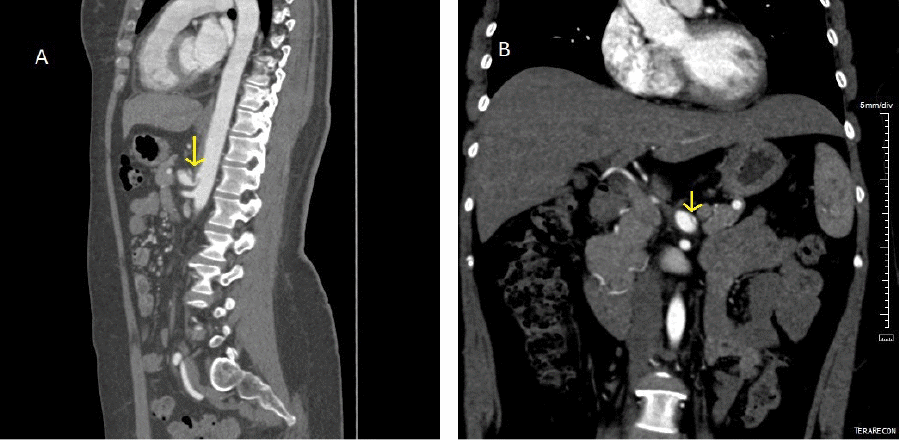

A 46-year-old female nonsmoker presented to the emergency department with acute onset of epigastric pain associated with abdominal bloating and generalized weakness. She noted postprandial pain and nausea while reported having two prior episodes of similar but less intense abdominal pain the preceding week. Her past medical history was notable for anxiety and depression, vasovagal syncope, endometriosis, gastroesophageal reflux disease, chronic constipation, scoliosis, kyphosis, and FBN1 gene variance of unknown significance. Surgical history included multiple operations for endometriosis, transabdominal hysterectomy, and ventral hernia repair. On physical exam, her vitals were normal, and her abdomen was soft, nontender, and nondistended. Right upper quadrant ultrasound demonstrated celiac and proximal splenic artery thrombosis and chronic median arcuate ligament compression of the celiac artery, which was noted to be ectatic. Computed tomography angiography (CTA) showed a 2.9 × 1.3 cm mass near the posterior aspect of the pancreatic body described to be occluding the proximal splenic artery, which raised suspicion for malignancy. Triple-phase enhanced computed tomography (CT) of the abdomen and pelvis demonstrated median arcuate ligament compression with severe celiac artery stenosis (approximately 85%) and post-stenotic dilation, while the posterior pancreatic mass noted on CTA was clarified to be inflammatory thickening of the celiac artery bifurcation (Figure 1A). A dissection of the celiac artery was identified to extend from the poststenotic dilation into the common hepatic artery (Figure 1B). The common hepatic artery was found to be completely occluded with reconstitution of the proper hepatic via collaterals from the gastroduodenal artery. Abdominal Doppler ultrasound (DUS) was performed, confirming median arcuate ligament compression, with celiac axis supine velocities of 455 cm/sec on expiration, 157 cm/sec on inspiration, and 557 cm/sec at rest.

Figure 1. Sagittal and Coronal CTA Images. Published with Permission

A) Note median compression ligament compression of celiac artery (arrow); and B) celiac artery dissection (arrow)